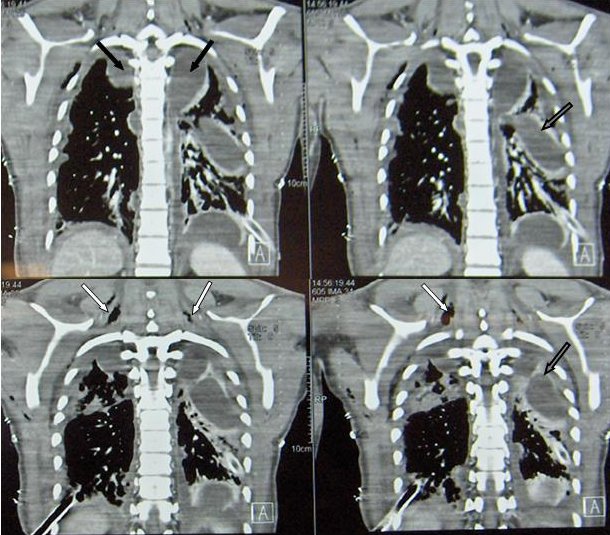

Despite the above management, the patient’s condition rapidly deteriorated, and he required endotracheal intubation and mechanical ventilation. Pain and swelling in the neck developed and a CT scan of the neck and thorax (Figure 2) demonstrated multiple cervical (white arrows) and mediastinal abscesses (black arrows) as well as bilateral empyema, (open arrows) leading to the diagnosis of descending necrotizing mediastinitis.